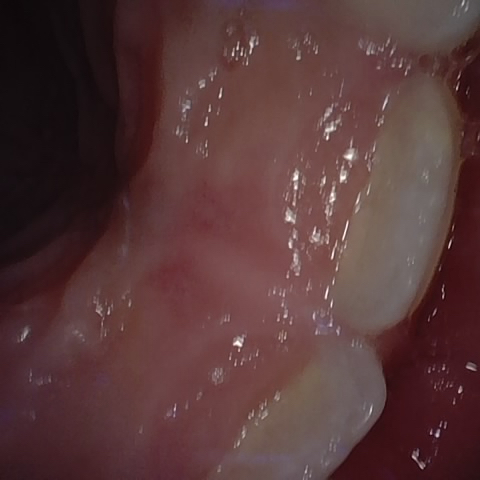

Annotated as "Good"